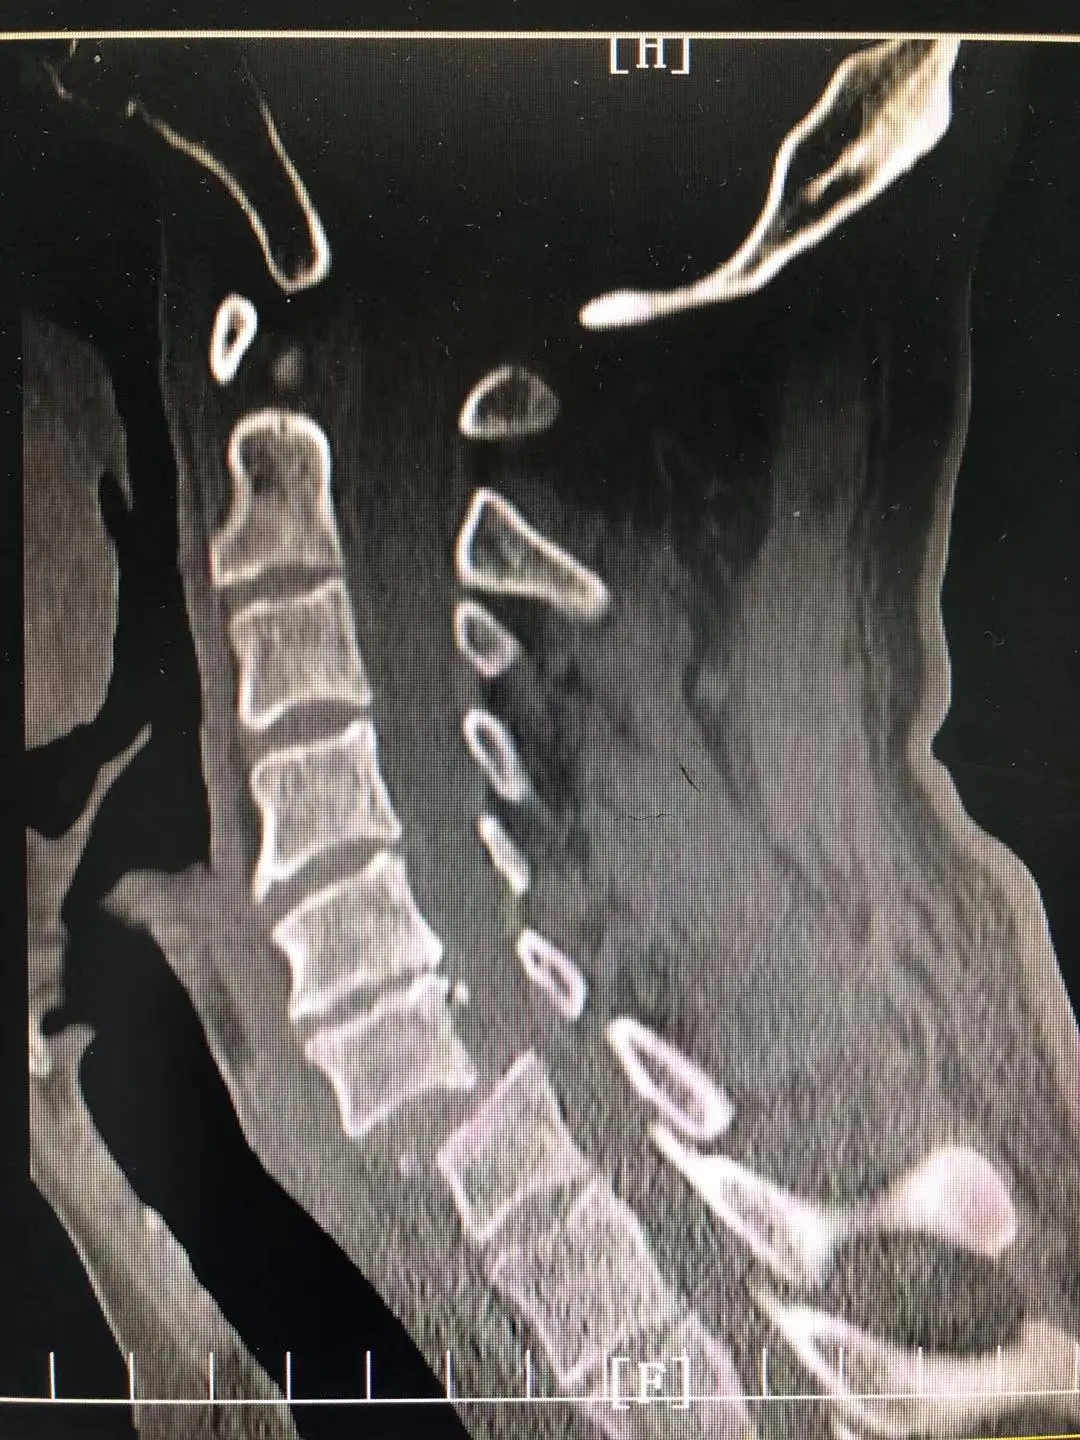

患者因跌倒致颈6椎体滑脱伴高位截瘫入院。骨科主管医生李健见患者面容痛苦、四肢感觉运动障碍,遂一边询问患者病情,一边为患者查体。查体显示,患者从双侧乳头以下皮肤感觉丧失,双上肢肘腕关节尚能屈曲,双手及双下肢感觉运动完全丧失。经判断患者有严重的颈脊髓损伤,需尽快进行手术治疗。

为确保手术顺利开展,科室团队反复斟酌、制订手术方案后,在院本部脊柱外科郝杰教授的指导下,进行了“经颈椎后路椎管减压+颈5.6.7椎体侧块螺钉融合固定+经前路颈5.6椎间盘摘除、椎管减压、椎间植骨融合、内固定”手术。经过近5个小时手术,患者手术顺利,术后病情无反复,持续治疗中。

术后